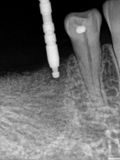

fredlibc | all galleries >> Galleries >> MKim - impl 45 and 46 > R4.jpg

R4.jpg